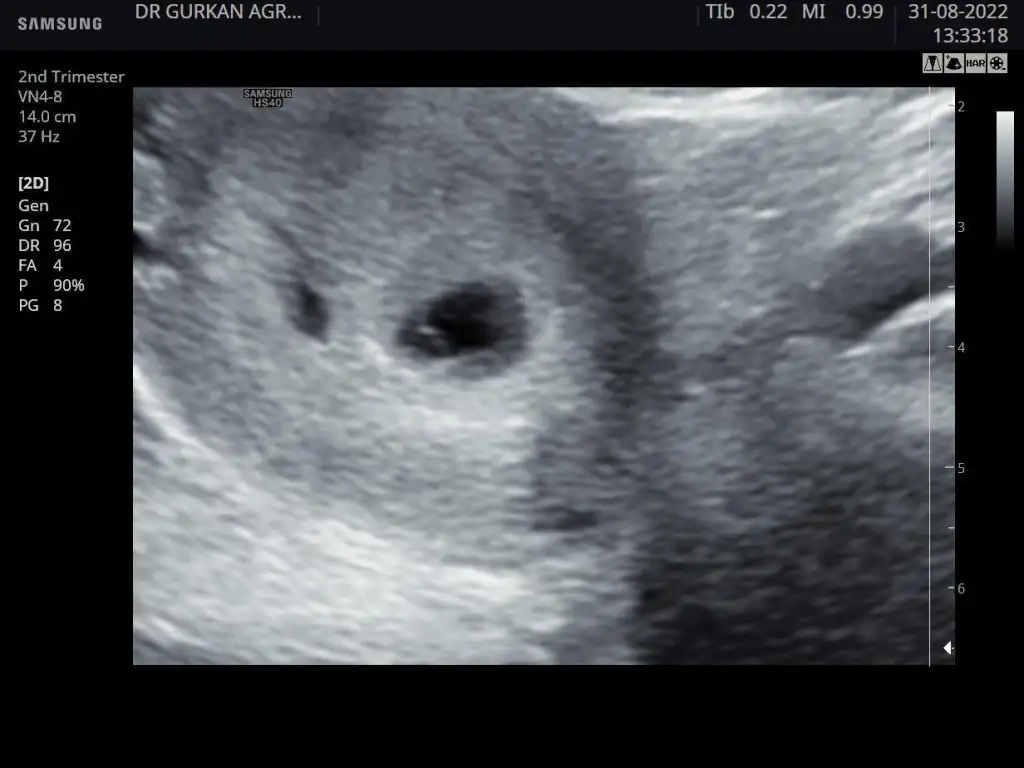

Herkese merhaba bugün ilk kontolüme gittim. Bebek ve kese gözüktü. Kalp atısı için haftaya gideceğim. Ama canım sıkıldı kanama alanı varmıs kese etrafında ultrasonda gözüktü. Progestan başladım bugün. Kanaması gözüküp progestan kullanınca sonra düzelen oldumu aranızda :KK43:

ultrason fotoğrafımıda ekliyorum. Soldaki karartı kanamalı alan